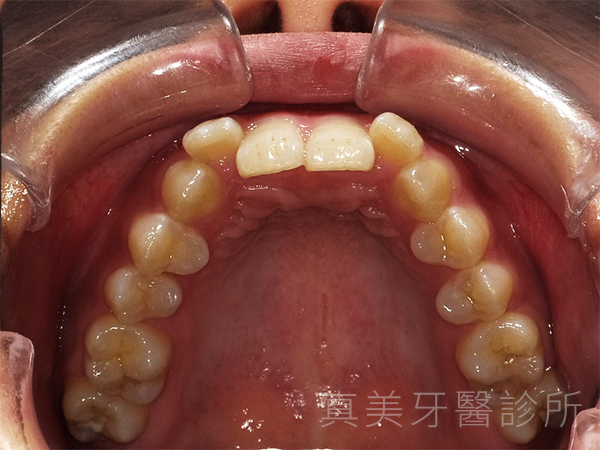

洪小姐是一位學生,平時很喜歡和同學一起參與社團活動,也常需要上台報告或參加課堂討論。對她而言,自信的笑容不只是人際互動的加分,更是展現青春活力的重要部分。不過,她一直對自己的牙齒不太滿意:正中門牙略微內凹、側門牙有些外凸,牙弓也偏狹窄,使得笑容看起來不夠自然,清潔上也較為不便。久而久之,她開始變得不太敢在合照時大方露齒微笑。

經過療程後,洪小姐的牙齒排列整齊了許多,原本外凸的門牙消失了,牙弓也變得更寬更自然。她開心地說,現在不但更喜歡照鏡子,也在合照時勇敢露齒微笑,甚至開始更積極參與各種社交場合。